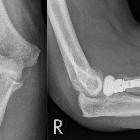

- radial head replacement

- for complex radial head fractures

- radiocapitellar prosthetic arthroplasty is also possible

Imaging evaluation usually requires AP and lateral views, and focuses on looking for loosening or periprosthetic fracture:

- loosening may be difficult to detect in radial head replacements using conventional radiography